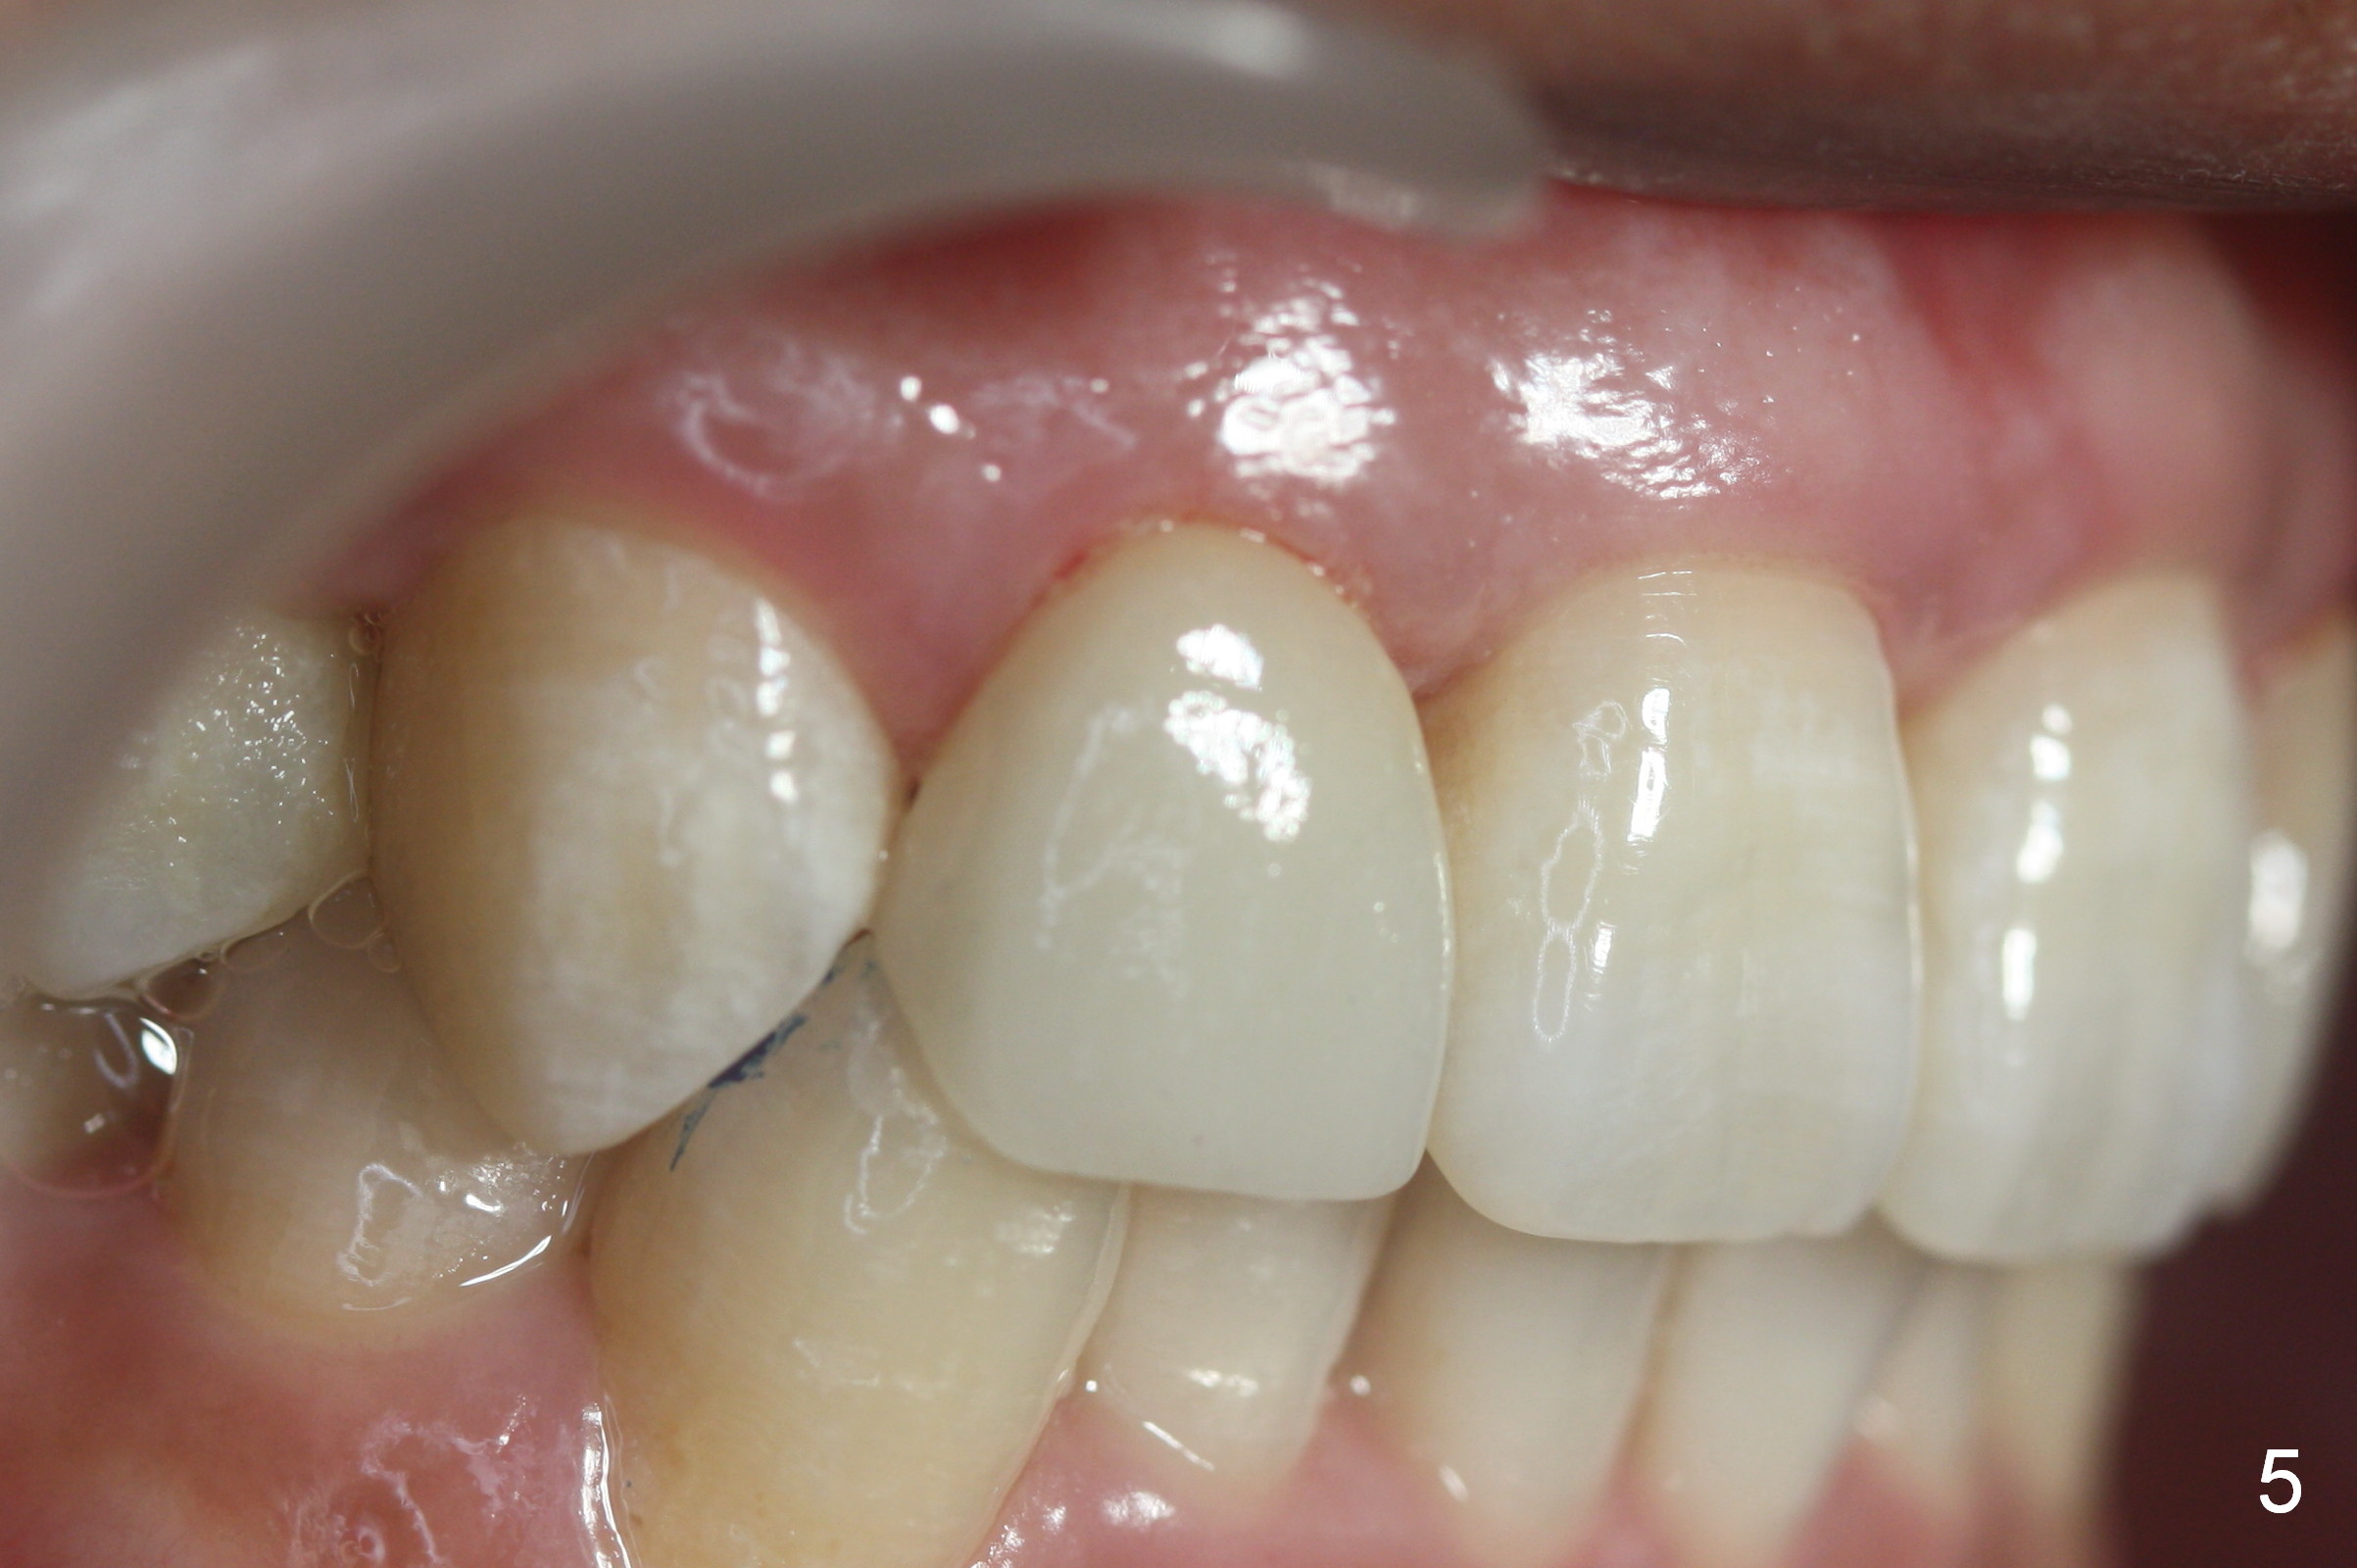

A 36-year-old man has 2 small, congenitally deformed lateral incisors (peg laterals, Fig.1,2 *). After discussion, we choose porcelain veneers for cosmetic makeup. The teeth need minor shaving (Fig.3,4); right colors are being selected with a shade guide (Fig.4: G). The shaving is so conservative that there is no pain during the procedure and there is no need to make temporary veneers. One to 2 weeks later, porcelain veneers are cemented (Fig.5,6). The patient is satisfied.

In brief, porcelain veneers takes two visits to finish. They looks more natural. The color stays longer than resin ones.